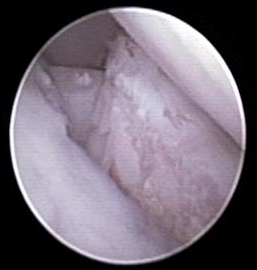

Somit stand die Diagnose „abgebrochener innerer Kronfortsatz“ (fragmentierter Processus coronoideus medialis ulnae) als Ursache für die Lahmheit bei „Oscar“ fest. Diese Erkrankung zählt zum Formenkreis der Ellbogengelenkdysplasie und ist eine der häufigsten Lahmheitsursachen der Vordergliedmaße beim großwüchsigen Hund. Da das Belassen des abgebrochenen Kronfortsatzes die Arthrosebildung begünstigt, haben wir in der gleichen Narkose das Bruchstück arthroskopisch entfernt.